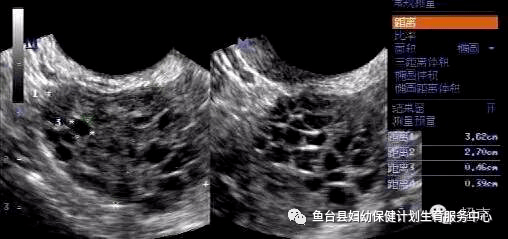

>ω< 这4种内分泌失调疾病会导致不孕!内分泌系统调节着整个身体机能的正常运行,通过下丘脑-垂体-卵巢轴调节,其中卵巢是女性的性腺,关系到女性的生育及正常的生理的功能(月经),所以若是与之相关的内分泌疾病会直接引发不孕。 01 多囊卵巢综合征 这个是比较直接的因素,它的表现为卵巢内的卵泡发育异常(卵泡数量太多...

˙▂˙ 警惕!这四种内分泌失调疾病,竟可能成为孕育生命的“拦路虎”!01 多囊卵巢综合征 这是一种较为直接导致女性不孕的因素。具体表现为卵巢内的卵泡发育出现异常情况,例如卵泡数量过多,而营养供给却不足,以至于无法支撑优势卵泡的正常形成,进而导致卵子无法正常排出,精子也就无法完成受精过程。从这类女性的体征来看,通常会伴有月经紊乱的...